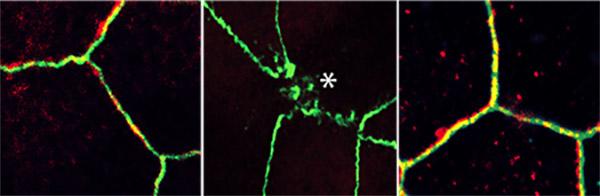

To simulate leaky gut conditions, the researchers rolled open the mini-gut balls to expose the surface of the intestinal lining. Then they sprinkled on several types of bacteria, which stressed the gut lining junctions, causing them to fall apart.

With this new model, Ghosh, Das and team confirmed that the junctions between cells are controlled by the previously identified stress-polarity signaling pathway. They discovered that the pathway keeping the gut lining intact begins to break down with aging and as colorectal tumors develop. They also measured an increase in markers of inflammation as the gut barrier began to fail.

But this stress-polarity signaling pathway can be restored, the team found. The diabetes drug metformin activates AMPK, an enzyme that plays a key role in the stress-polarity signaling pathway. The researchers demonstrated that metformin strengthens the junctions of mini-guts, tightening the lining back up when stressed by bacteria, aging or tumor formation. One measure of stress-polarity signaling pathway strength is the levels of a molecule called occludin. In Ghosh and Das' experiments, metformin increased occludin levels as much as six-fold compared to untreated cells.